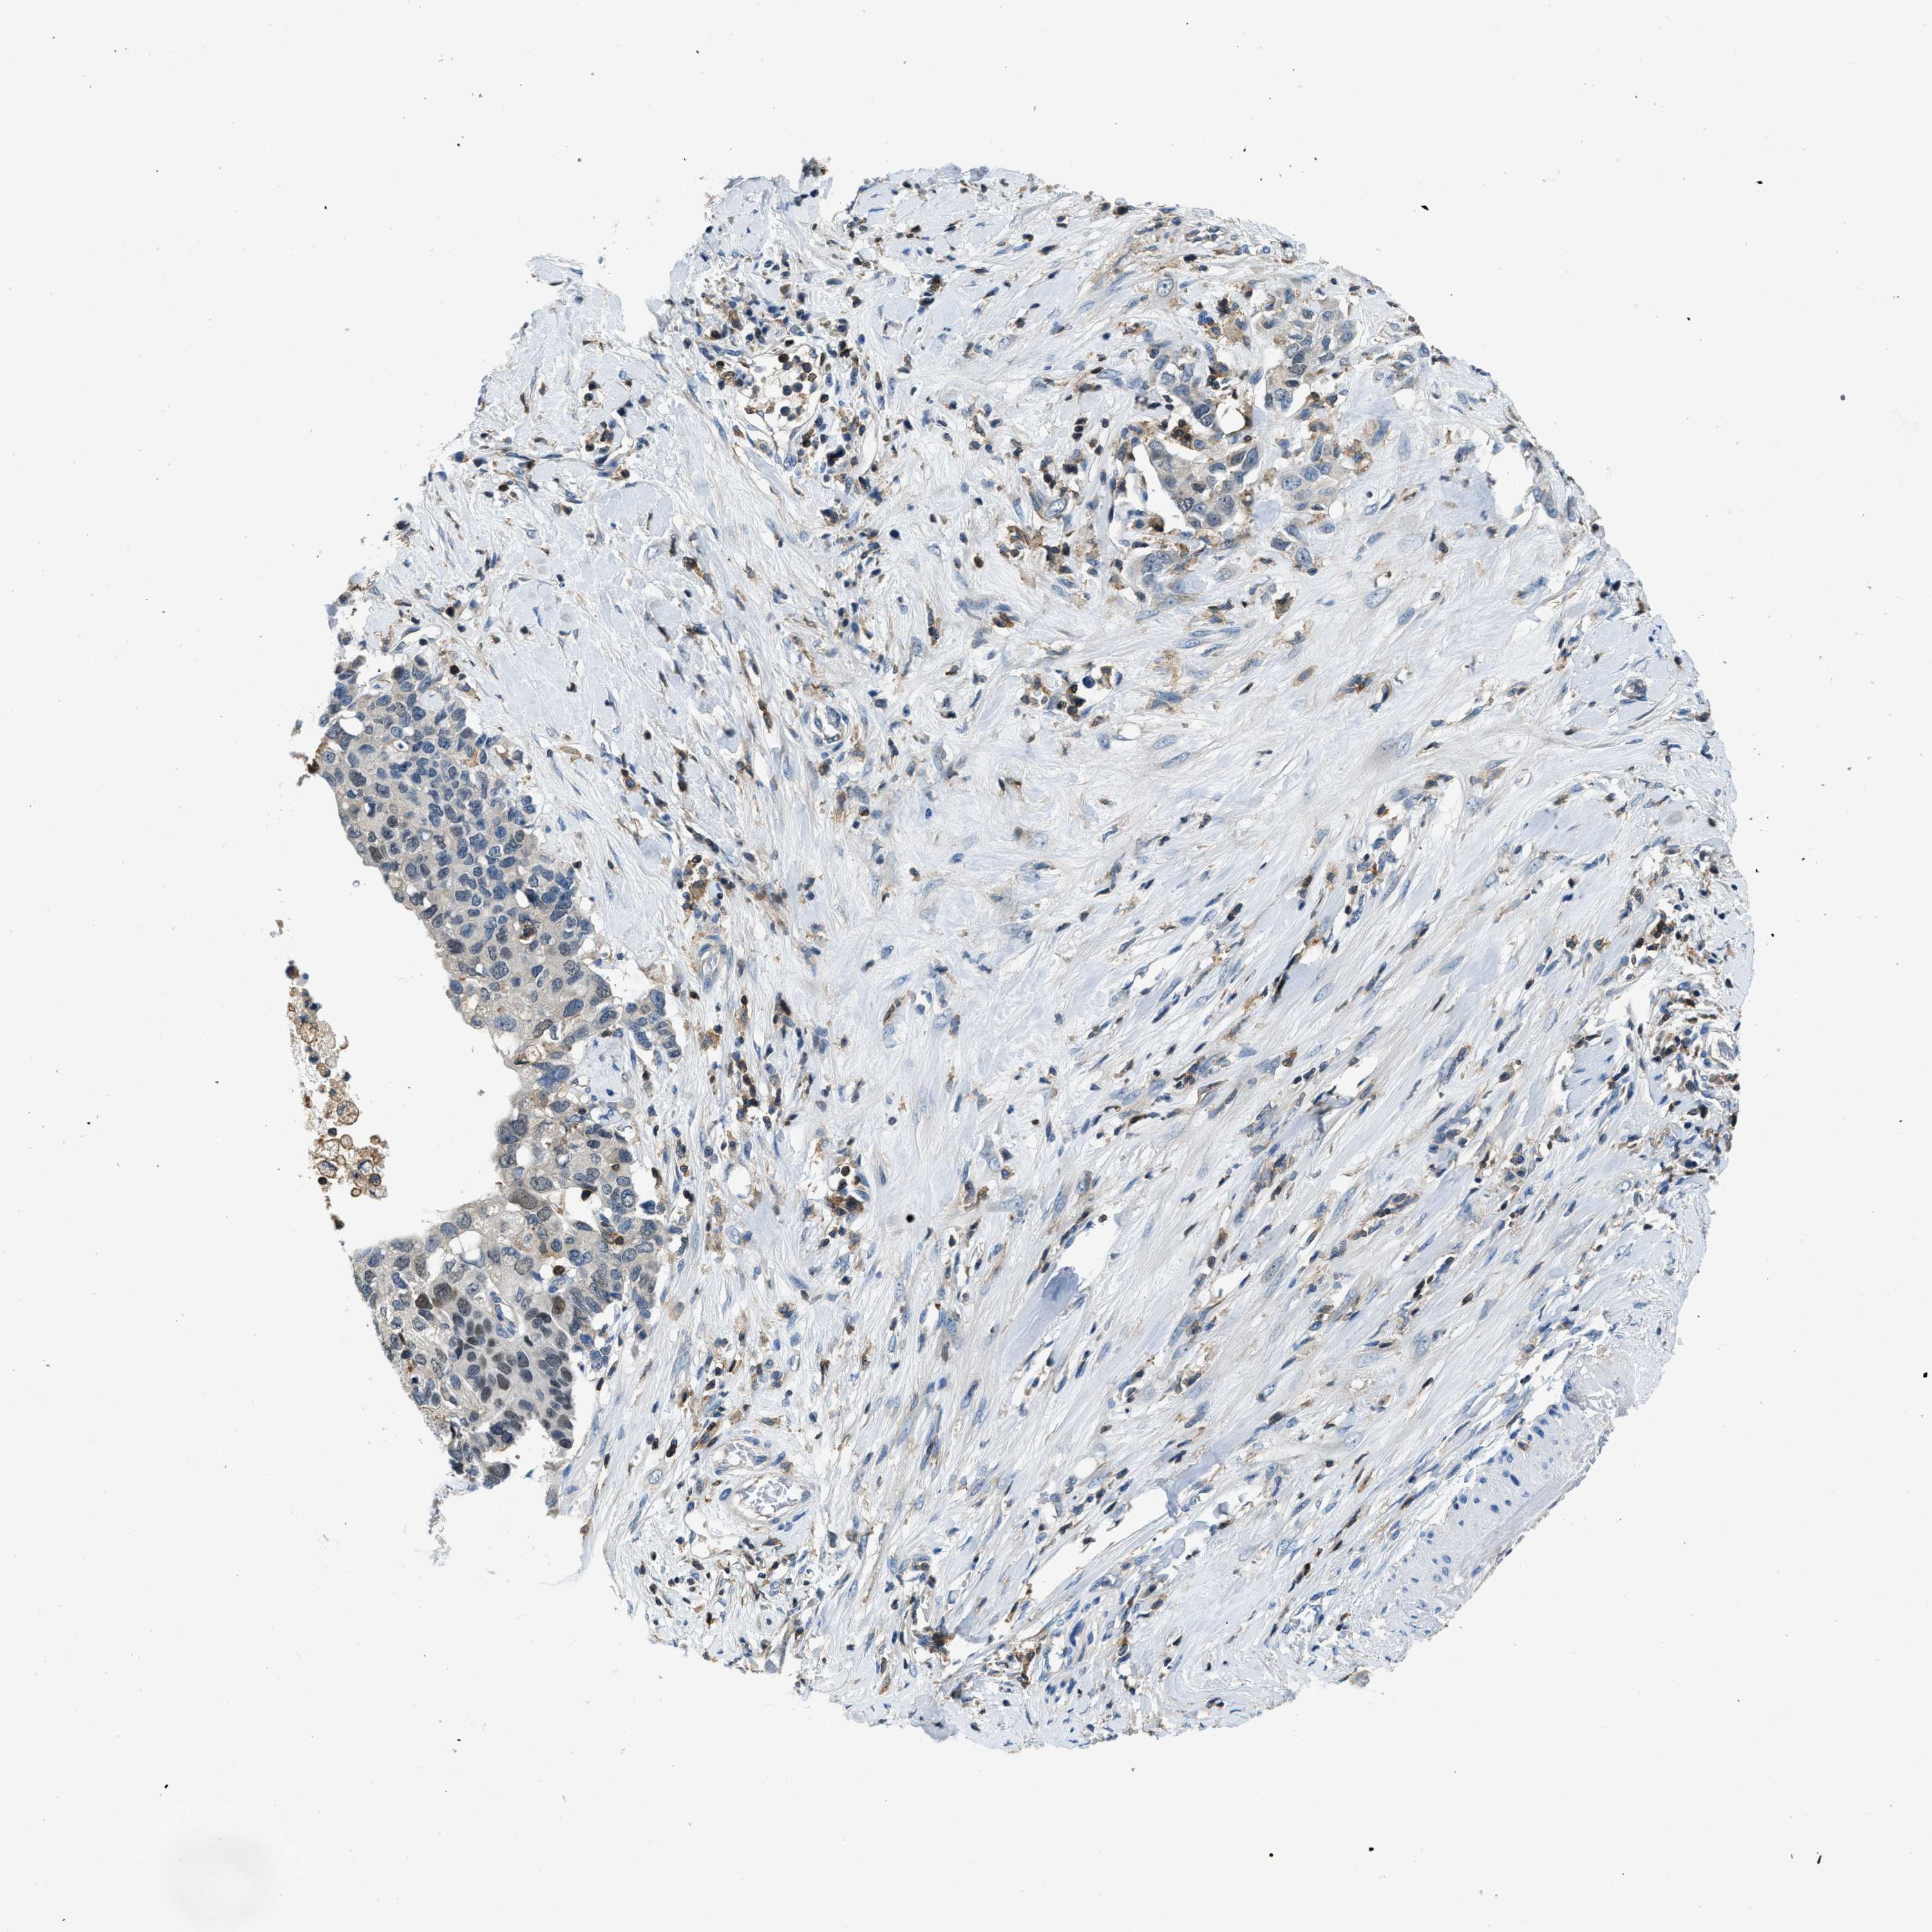

PANCREATIC CANCER - Protein expressioni

A mouse-over function shows sample information and annotation data. Click on an image to view it in a full screen mode. Samples can be filtered based on level of antibody staining by selecting one or several of the following categories: high, medium, low and not detected. The assay and annotation is described here.

Note that samples used for immunohistochemistry by the Human Protein Atlas do not correspond to samples in the TCGA dataset.

Antibody stainingi

Antibody staining in the annotated cell types in the current human tissue is reported as not detected, low, medium, or high, based on conventional immunohistochemistry profiling in selected tissues. This score is based on the combination of the staining intensity and fraction of stained cells.

Each image is clickable and will lead to virtual microscopy that enables deeper exploration of all samples and also displays staining intensity scores, fraction scores and subcellular localization as well as patient and tissue information for each sample.

Antibody HPA021252

Staining

High

Medium

Low

Not detected

Intensity

Strong

Moderate

Weak

Negative

Quantity

>75%

75%-25%

<25%

None

Location

Nuclear

Cytoplasmic/membranous

Cytoplasmic/membranous,nuclear

Adenocarcinoma, NOS